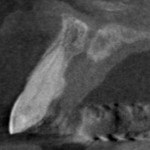

The lateral images taken with the Kodak 9000 CBCT showed a different story however. All the 0.076 mm sections showed a normal periodontal ligament space surrounding tooth #11 (and tooth #21). There was however a slightly enlarged incisive canal situated palatally, directly behind the root of tooth #11. The two-dimensional image overlayed the root on the incisive canal and gave the appearance of a periapical radiolucency usually seen with chronic apical periodontitis.

Combining the patient’s history with clinical tests and appropriate imaging led us to a normal pulpal and periapical diagnosis for tooth #11 (and #21). No treatment was required for tooth #11 in this case. There is a possibility that the somewhat enlarged incisive canal was a nacient nasoplanatine duct cyst.

Enlarged incisive canals, also known as nasopalantine duct cysts (NPDC), are developmental, epithelial, non-neoplastic cysts. They are the most common non-odontogenic cysts in the mouth (33-72% of non-odontogenic lesions). NPDC are believed to occur during secondary palate formation at between 8 and 12 weeks of intrauterine life.

Due to the small size of the incisive canal and absence of symptoms the decision was made to monitor the area with annual images to determine any changes which may occur. Further enlargement of the area may indicate a need for removal of the lesion.